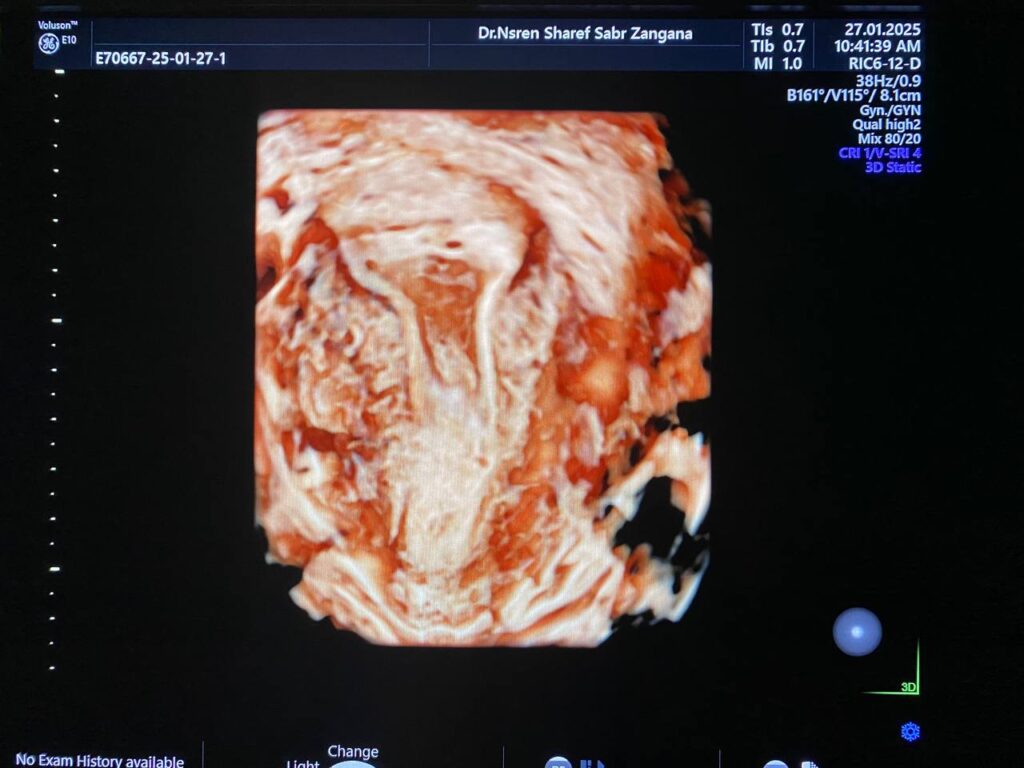

Heterogenous avascular endometrial thickening ( blood clot?) with Presence of hypoechoic vascular (score 4 ) mass within the distal part of the cervix (at level of external os), it’s size 15x15mm , its arise ( single pedicle vascular ) from upper cervical canal nearly (at level of internal os) , mostly pedunculated submucosal fibroid ? polyp? other cervical mass